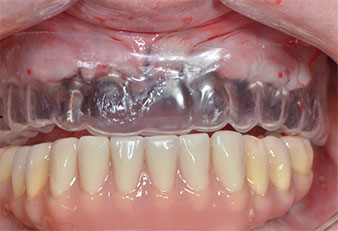

Три години по-късно е дошло времето за максиларна протеза от същия тип. Въз основа на планирането със CBCT, аугментацията на синусите е избегната с помощта на къси импланти и използването на хирургичен шаблон, за да се прехвърлят планираните позиции в алвеоларния гребен. (Фиг. 1 и 2).

Поради сравнително твърдата кост (D2) в тази област, 10-милиметровото имплантно ложе в позиции 11 и 21 беше завършено с ротационен дрил с диаметър 4 mm в комбинация с W&H хирургичен обратен наконечник WS-75 L, W&H имплантологичен мотор Implantmed и опционалния W&H Osstell ISQ модул. За разлика от това, благодарение на меката кост, дисталните зони се подготвят до окончателен диаметър 3 mm, използвайки накрайник за Piezomed I3P. Имплантите най-накрая са поставени трансгингивално, за да остеоинтегрират за три месеца (Фиг. 6-10). Съществуващата протеза се фиксира на четирите временни импланта (Фиг. 8).